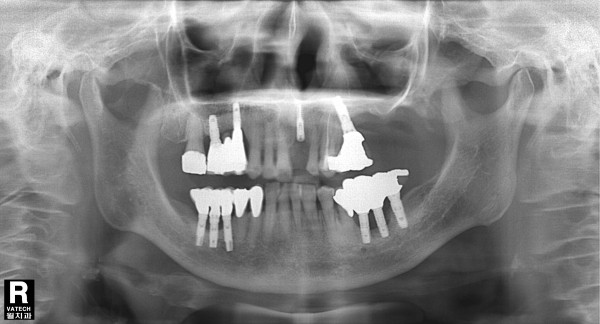

89세여자환자 / 좌측하악구치부 임플란트제거후 뼈이식 및 재식립